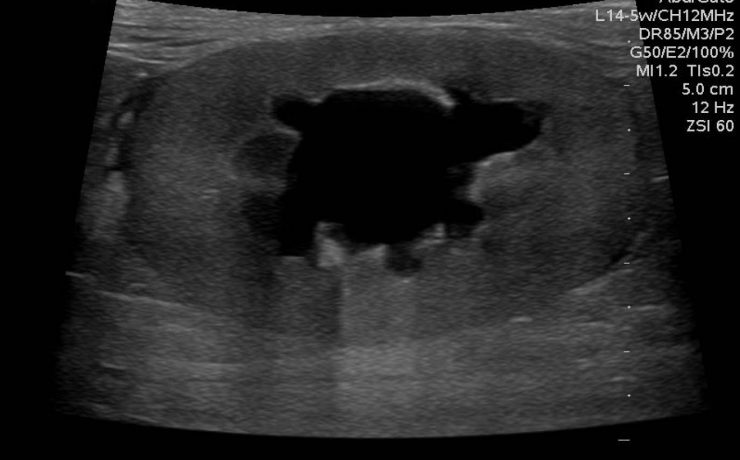

El estudio ultrasonográfico de la vía biliar requiere que el paciente este en ayunas de 6 horas, puesto que la ingesta de alimentos, sobre todo de naturaleza grasa, provoca la contracción o el colapso de la vesícula biliar, también reduce el gas intestinal que dificulta la evaluación ecográfica de la